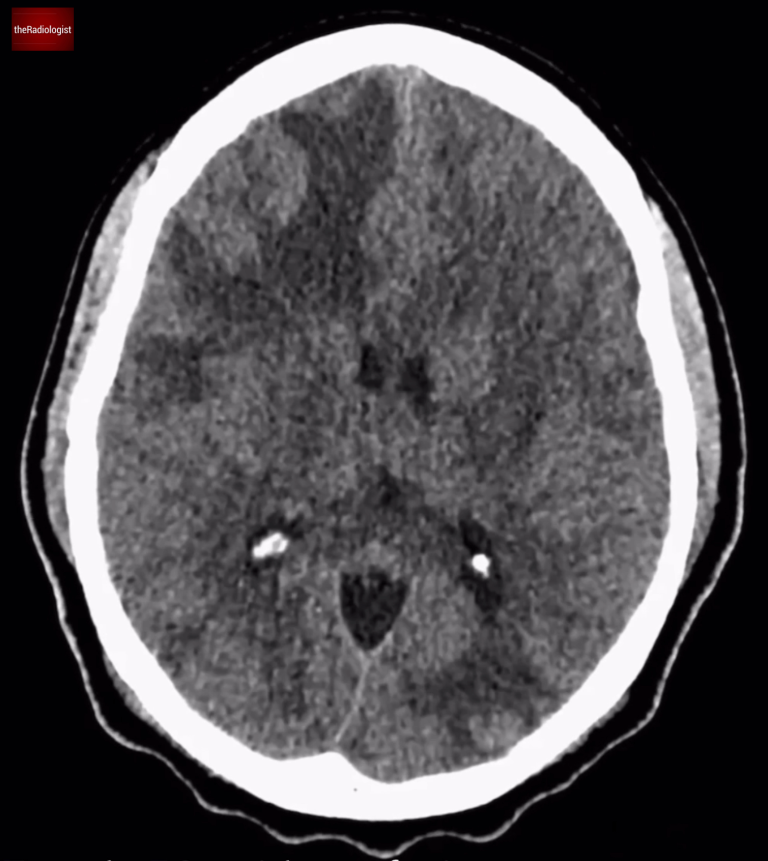

Non contrast CT head, complete scan.

Returning to our case, the administration of IV contrast highlights multiple ring enhancing lesions distributed throughout the brain. These ring-enhancing lesions have a differential diagnosis, famously known as ‘MAGIC DR’.

The reason I like this differential is that the top two causes make up the majority of ring enhancing cases we see in every day practice. That is, you can account for most cases by malignancy (more often metastases) and infection, ie abscess formation.